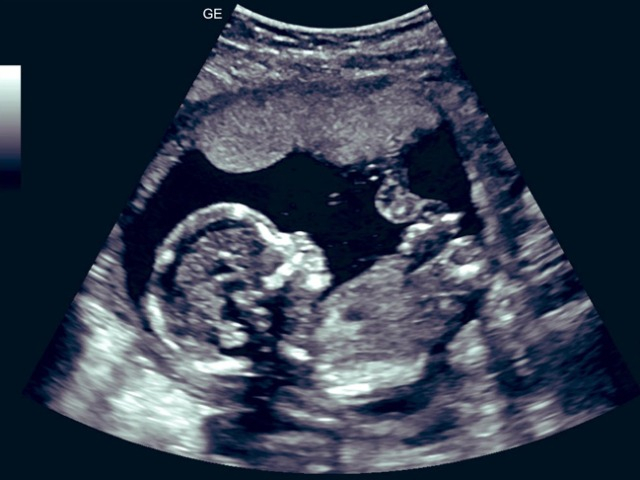

Ảnh minh họa